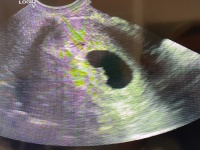

Ma voltam dokinál. 5+5 :) Hallottuk a szívhangot is :)